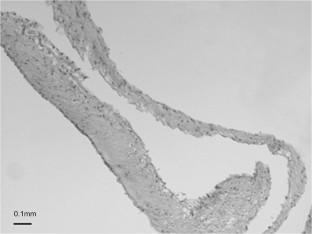

Arachnoid samples of 162 consecutive foramen magnum decompressions from 2006 to 2016 were studied. Arachnoid thickness and degrees of fibrosis and cellularity were determined with the examiner blinded for clinical data. Based on 145 first time decompressions, a histological classification for arachnoid features was developed.

The arachnoid was thicker in secondary compared with primary decompressions (176.1 ± 158.2 μm vs. 35.9 ± 43.5 μm; p = 0.0026) and in adults compared to children (37.3 ± 45.3 μm vs. 21.8 ± 7.7 μm; p = 0.0007). In primary decompressions, arachnoid thickness, degrees of fibrosis, and cellularity followed a normal distribution with all features shifted significantly to higher grades in secondary decompressions. The histological classification correlated with the preoperative severity of gait ataxia, motor weakness, and sensory deficits, whereas it had no predictive power for postoperative short- or long-term results. By comparison, the intraoperative evaluation of arachnoid changes accounting for relationships between arachnoid and surrounding tissues showed higher correlations with preoperative symptoms and had significant predictive power for postoperative short- and long-term results.